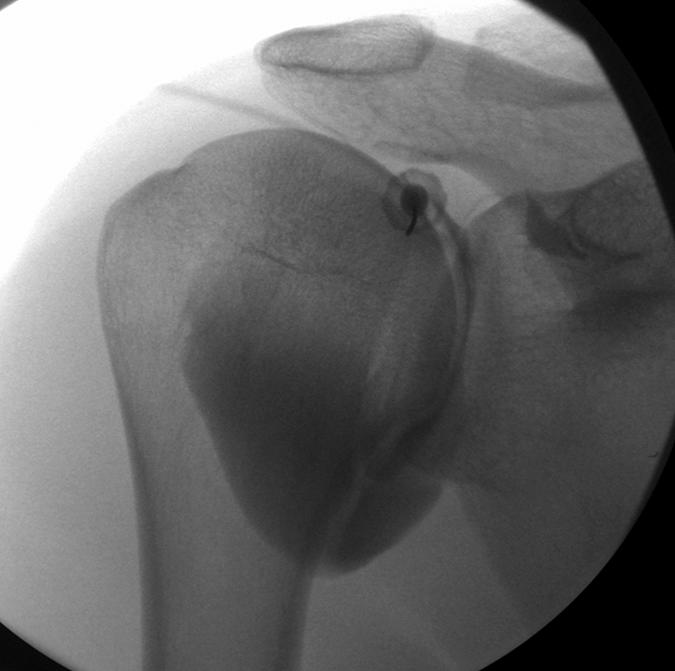

Therapeutic and diagnostic image-guided procedures

Dr Skiadas offers a wide range of image guided procedures in various body areas to treat a spectrum of musculoskeletal problems and aid the diagnosis of musculoskeletal pathologies.

Diagnostic interventions

Dr Skiadas specializes in musculoskeletal pathology and offers advanced musculoskeletal diagnostic interventions to expedit diagnosis and treatment

Therapeutic interventions

Dr Skiadas delivers a wide range of therapeutic interventions tailored to your problem using image guidance to ensure optimal outcome.